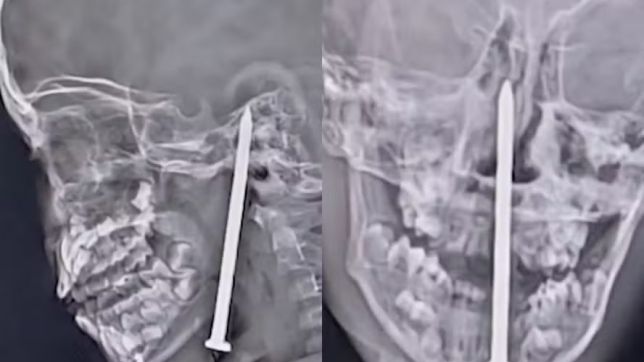

Menino de 7 anos sobrevive após ter prego de 7,5 centímetros preso no cérebro